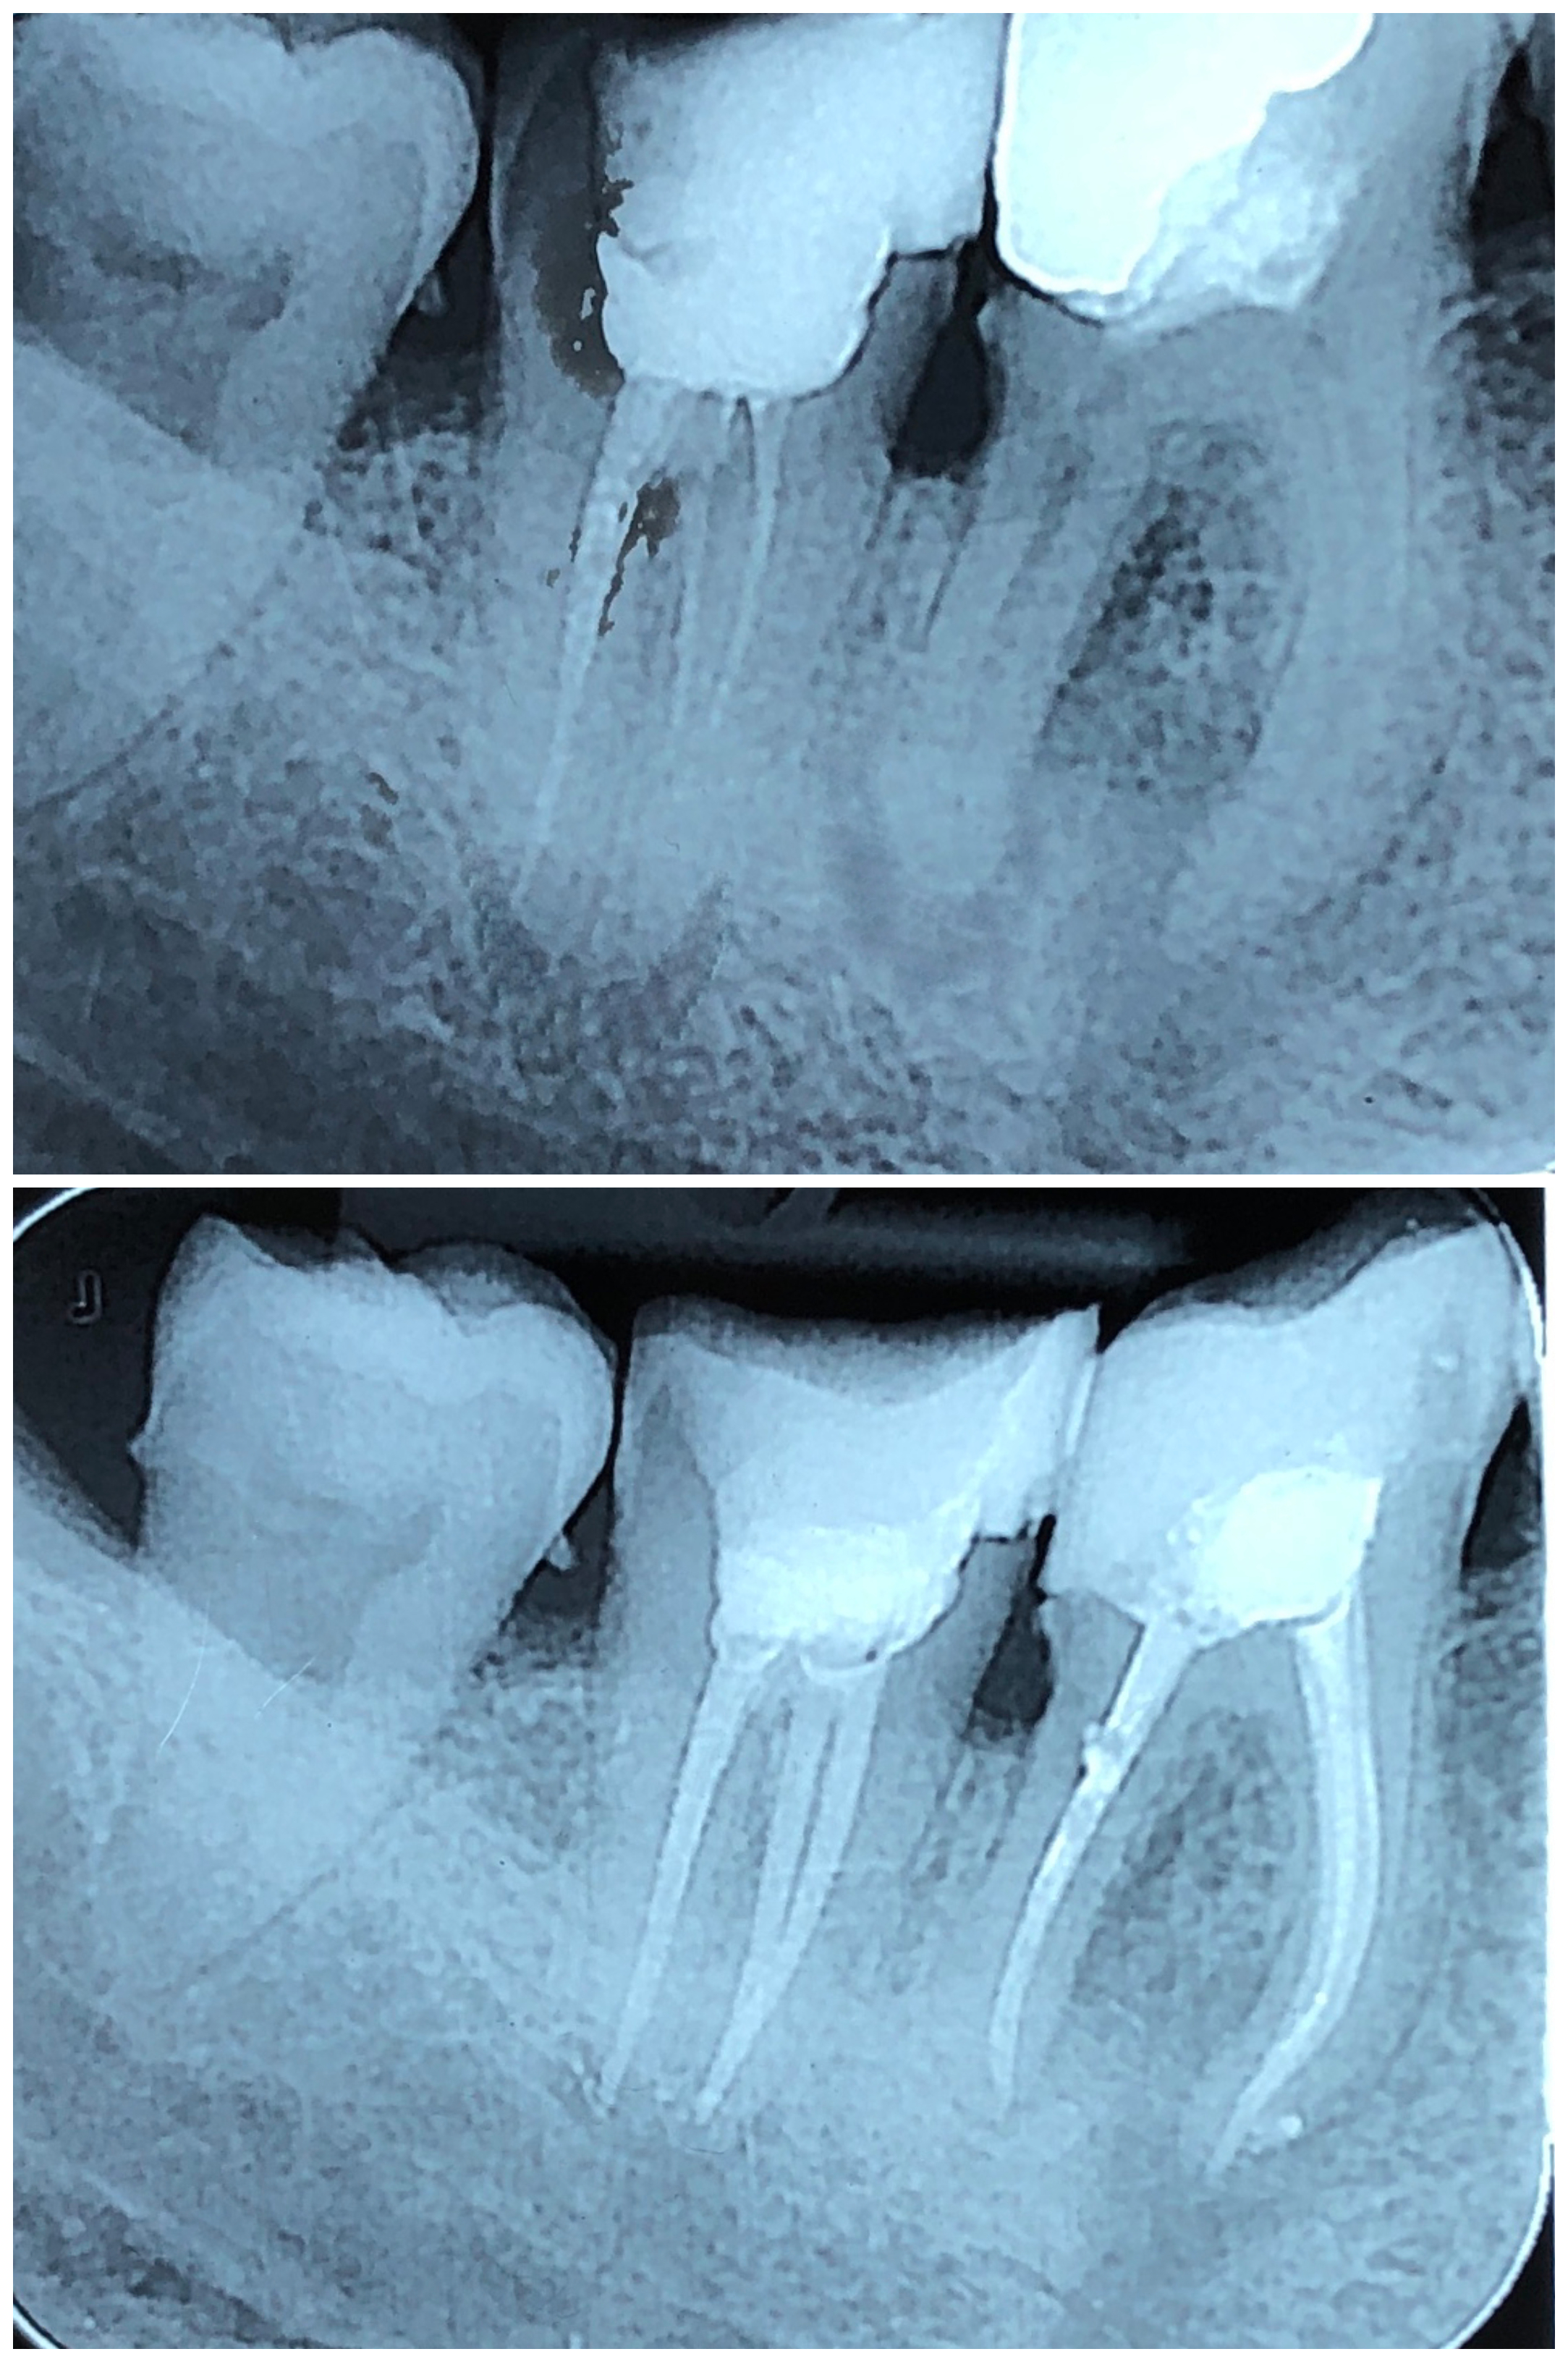

Endodontska terapija započinje uklanjanjem karijesom zahvaćenog zubnog tkiva, nakon čega se odstranjuje upaljena zubna pulpa te se kemijski i mehanički čisti zubni kanal radi uklanjanja bakterija i inficiranog dentina.

Ključ uspješnog liječenja je u primjeni strojne umjesto ručne obrade kanala.

Zato se u našoj ordinaciji primjenjuje najnoviji i tehnološki najmoderniji sustav strojne endodoncije – sustav Reciproc.

Reciproc predstavlja potpuno novi koncept u liječenju korijenskih kanala zuba. Postupak u kojem se primjenjuje ovaj sustav potpuno je siguran, brz, jednostavan i bezbolan. U većini slučajeva za liječenje zuba dovoljan je jedan posjet ordinaciji.